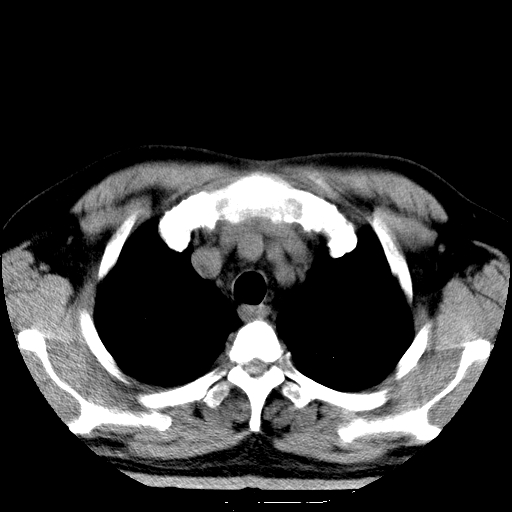

男,65岁,咳嗽、咳痰、发热5天。

慢支 肺间质纤维化合并感染!

支气管扩张合并感染,胸膜肥厚

考虑慢支并感染,肺间质纤维化。

两肺间质性炎症并感染

慢支,肺心病

支持慢性支气管炎伴感染,双侧少量胸腔积液.

两肺间质纤维化,支扩合并感染,双侧胸腔积液

感染,肺间质纤维化。

慢支 肺间质纤维化合并感染

支持慢性支气管、肺间质纤维化合并感染。

慢性支气管炎并感染,支扩,双侧少量胸腔积液.